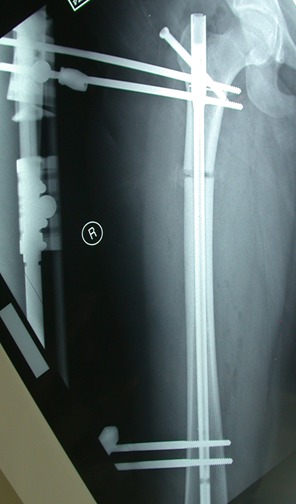

التطويل باستخدام المسامير النخاعية الداخلية ذاتية التطويل

وبدأ استخدام  تقنية المسمار النخاعي  من عام 2008م  أي  قبل استخدام هذه التقنية في الولايات المتحدة الامريكية بثلاث سنوات

وقد كان الاستخدام الاولي بجهاز الفت بون الالماني الرائد وقد تم عمل مئات العمليات بهذه التقنية, اضافة الى

استخدام مسمار البريسايز2 المتميز وكلاهما يعمل بالريموت كنترول ,

بالنسبة للفت بون يعمل بمجال الكهربائي الداخلي وموتور داخلي  بالمسمار, والبريسايز 2 يعمل باستخدام تقنية مغناطيس كبير الحجم خارجي في وحدة تدعى(ERC) لتحريك مغناطيس داخل المسمار يؤدي لتطويل المسمار عن طريق هذا التفاعل المغناطيسي.

ويستخدم في تعويض الطول في عظمة الساق والفخذ والعضد.